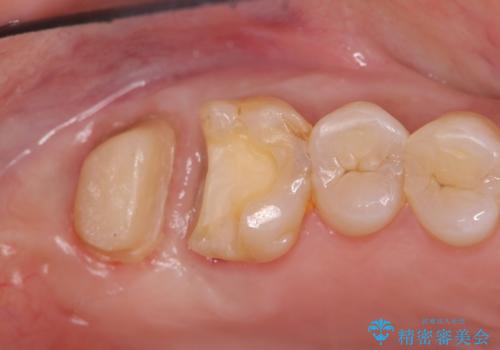

歯周外科、マイクロスコープを用いた虫歯治療を行い歯を残す治療計画を立てます。

深い虫歯には歯周外科、マイクロスコープを用いた丁寧な虫歯の除去を行うことで歯の神経や歯そのものを残すことが可能になります。